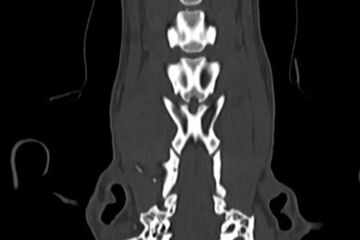

- Computertomographie

Neurochirurgie

Die Neurochirurgie beschäftigt sich mit der operativen Behandlung von Verletzungen, Fehlbildungen und Tumorerkrankungen des zentralen und peripheren Nervensystems.

Folgende Operationen an der Wirbelsäule werden in unserer Praxis durchgeführt:

- dorsale Laminektomie und Foraminotomie beim sogenannten Cauda-Equina-Kompressionssyndrom/Foraminostenose L7/S1

- dorsale Laminektomie bei einer OCD des Kreuzbeins

- Fixation von Wirbelfrakturen und Wirbelluxationen

- Hemilaminektomie (Bandscheibenoperation)

- Minihemilaminektomie (Bandscheibenoperation)

- partielle Korpektomie (Bandscheibenoperation)

- Tumoroperationen

- Ventral Slot (Bandscheibenoperation)